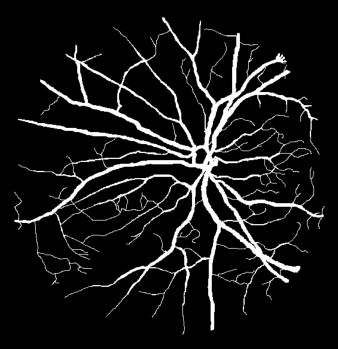

Semantic segmentation of blood vessels is an important task in medical image analysis, but its progress is often hindered by the scarcity of large annotated datasets and the poor generalization of models across different imaging modalities. A key aspect is the tendency of Convolutional Neural Networks (CNNs) to learn texture-based features, which limits their performance when applied to new domains with different visual characteristics. We hypothesize that leveraging geometric priors of vessel shapes, such as their tubular and branching nature, can lead to more robust and data-efficient models. To investigate this, we introduce VessShape, a methodology for generating large-scale 2D synthetic datasets designed to instill a shape bias in segmentation models. VessShape images contain procedurally generated tubular geometries combined with a wide variety of foreground and background textures, encouraging models to learn shape cues rather than textures. We demonstrate that a model pre-trained on VessShape images achieves strong few-shot segmentation performance on two real-world datasets from different domains, requiring only four to ten samples for fine-tuning. Furthermore, the model exhibits notable zero-shot capabilities, effectively segmenting vessels in unseen domains without any target-specific training. Our results indicate that pre-training with a strong shape bias can be an effective strategy to overcome data scarcity and improve model generalization in blood vessel segmentation.